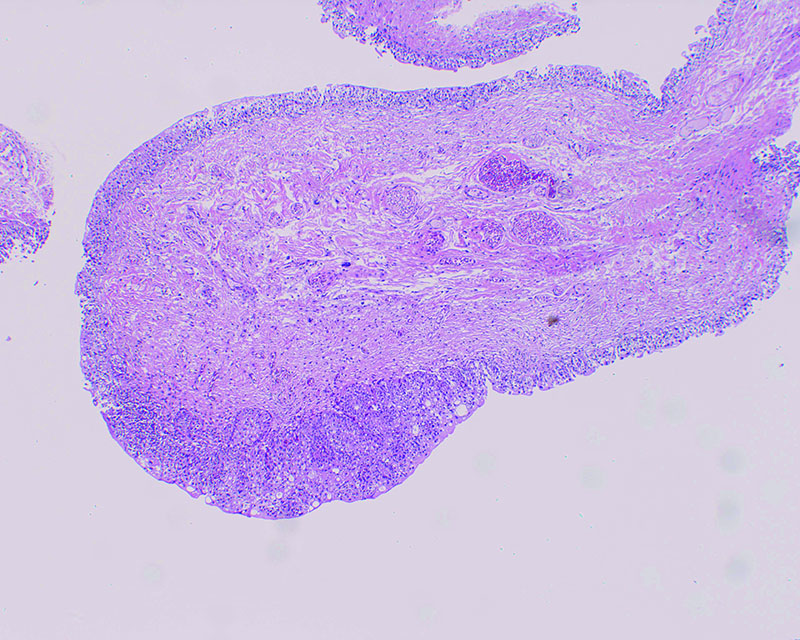

結節型・広基性 82歳・女性

通常光

NBI

病理 UC, pT1, High grade

コメント

通常光ではその辺縁がはっきりしない、丈の低い腫瘍。切除標本の病理組織診断はpT1であった。